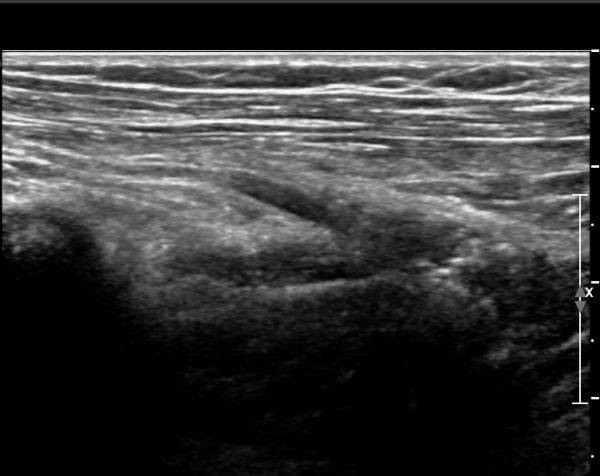

¿ä°ñ ¸ñ ºÎÀ§¿¡¼­ Èİñ°£½Å°æ Ⱦ´Ü¸é°Ë»ç»ó Èİñ°£½Å°æÀÇ Àú¿¡ÄÚ ºÎÁ¾ÀÌ °üÂûµÈ´Ù(»çÁø 2).

¾Æ·§ÆÈÀ» ȸ³»ÇÑ »óÅ¿¡¼­ Èİñ°£½Å°ßÁ¾´Ü¸é°Ë»ç»ó ȸ¿Ü±Ù ±ÙÀ§ºÎ¿¡¼­ Èİñ°£½Å°æÀÇ Àú¿¡ÄÚ

ºÎÁ¾ÀÌ °üÂûµÈ´Ù(»çÁø 3, 4).